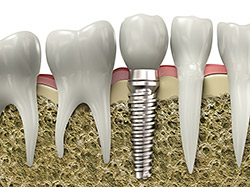

An implant is a synthetic tooth root in the shape of a post that is surgically placed into the jawbone. The “root” is usually made of titanium (the same material used in many replacement hips and knees), a metal that is well suited to pairing with human bone. A replacement tooth is then fixed to the post. The tooth can be either permanently attached or removable. Permanent teeth are more stable and feel more like natural teeth.